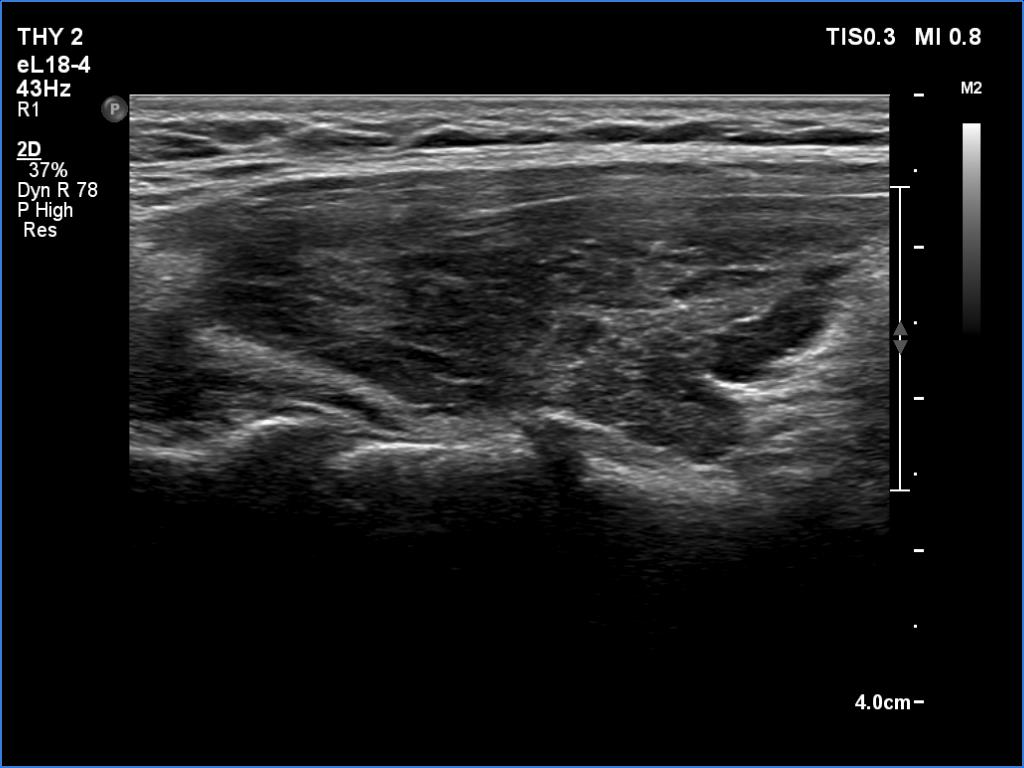

Right lobe, longitudinal scan

Right lobe, longitudinal scan. The echo structure remained normal in only small islets.